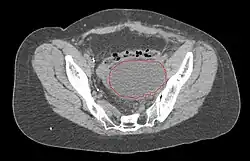

- Postoperative Lymphocele

-